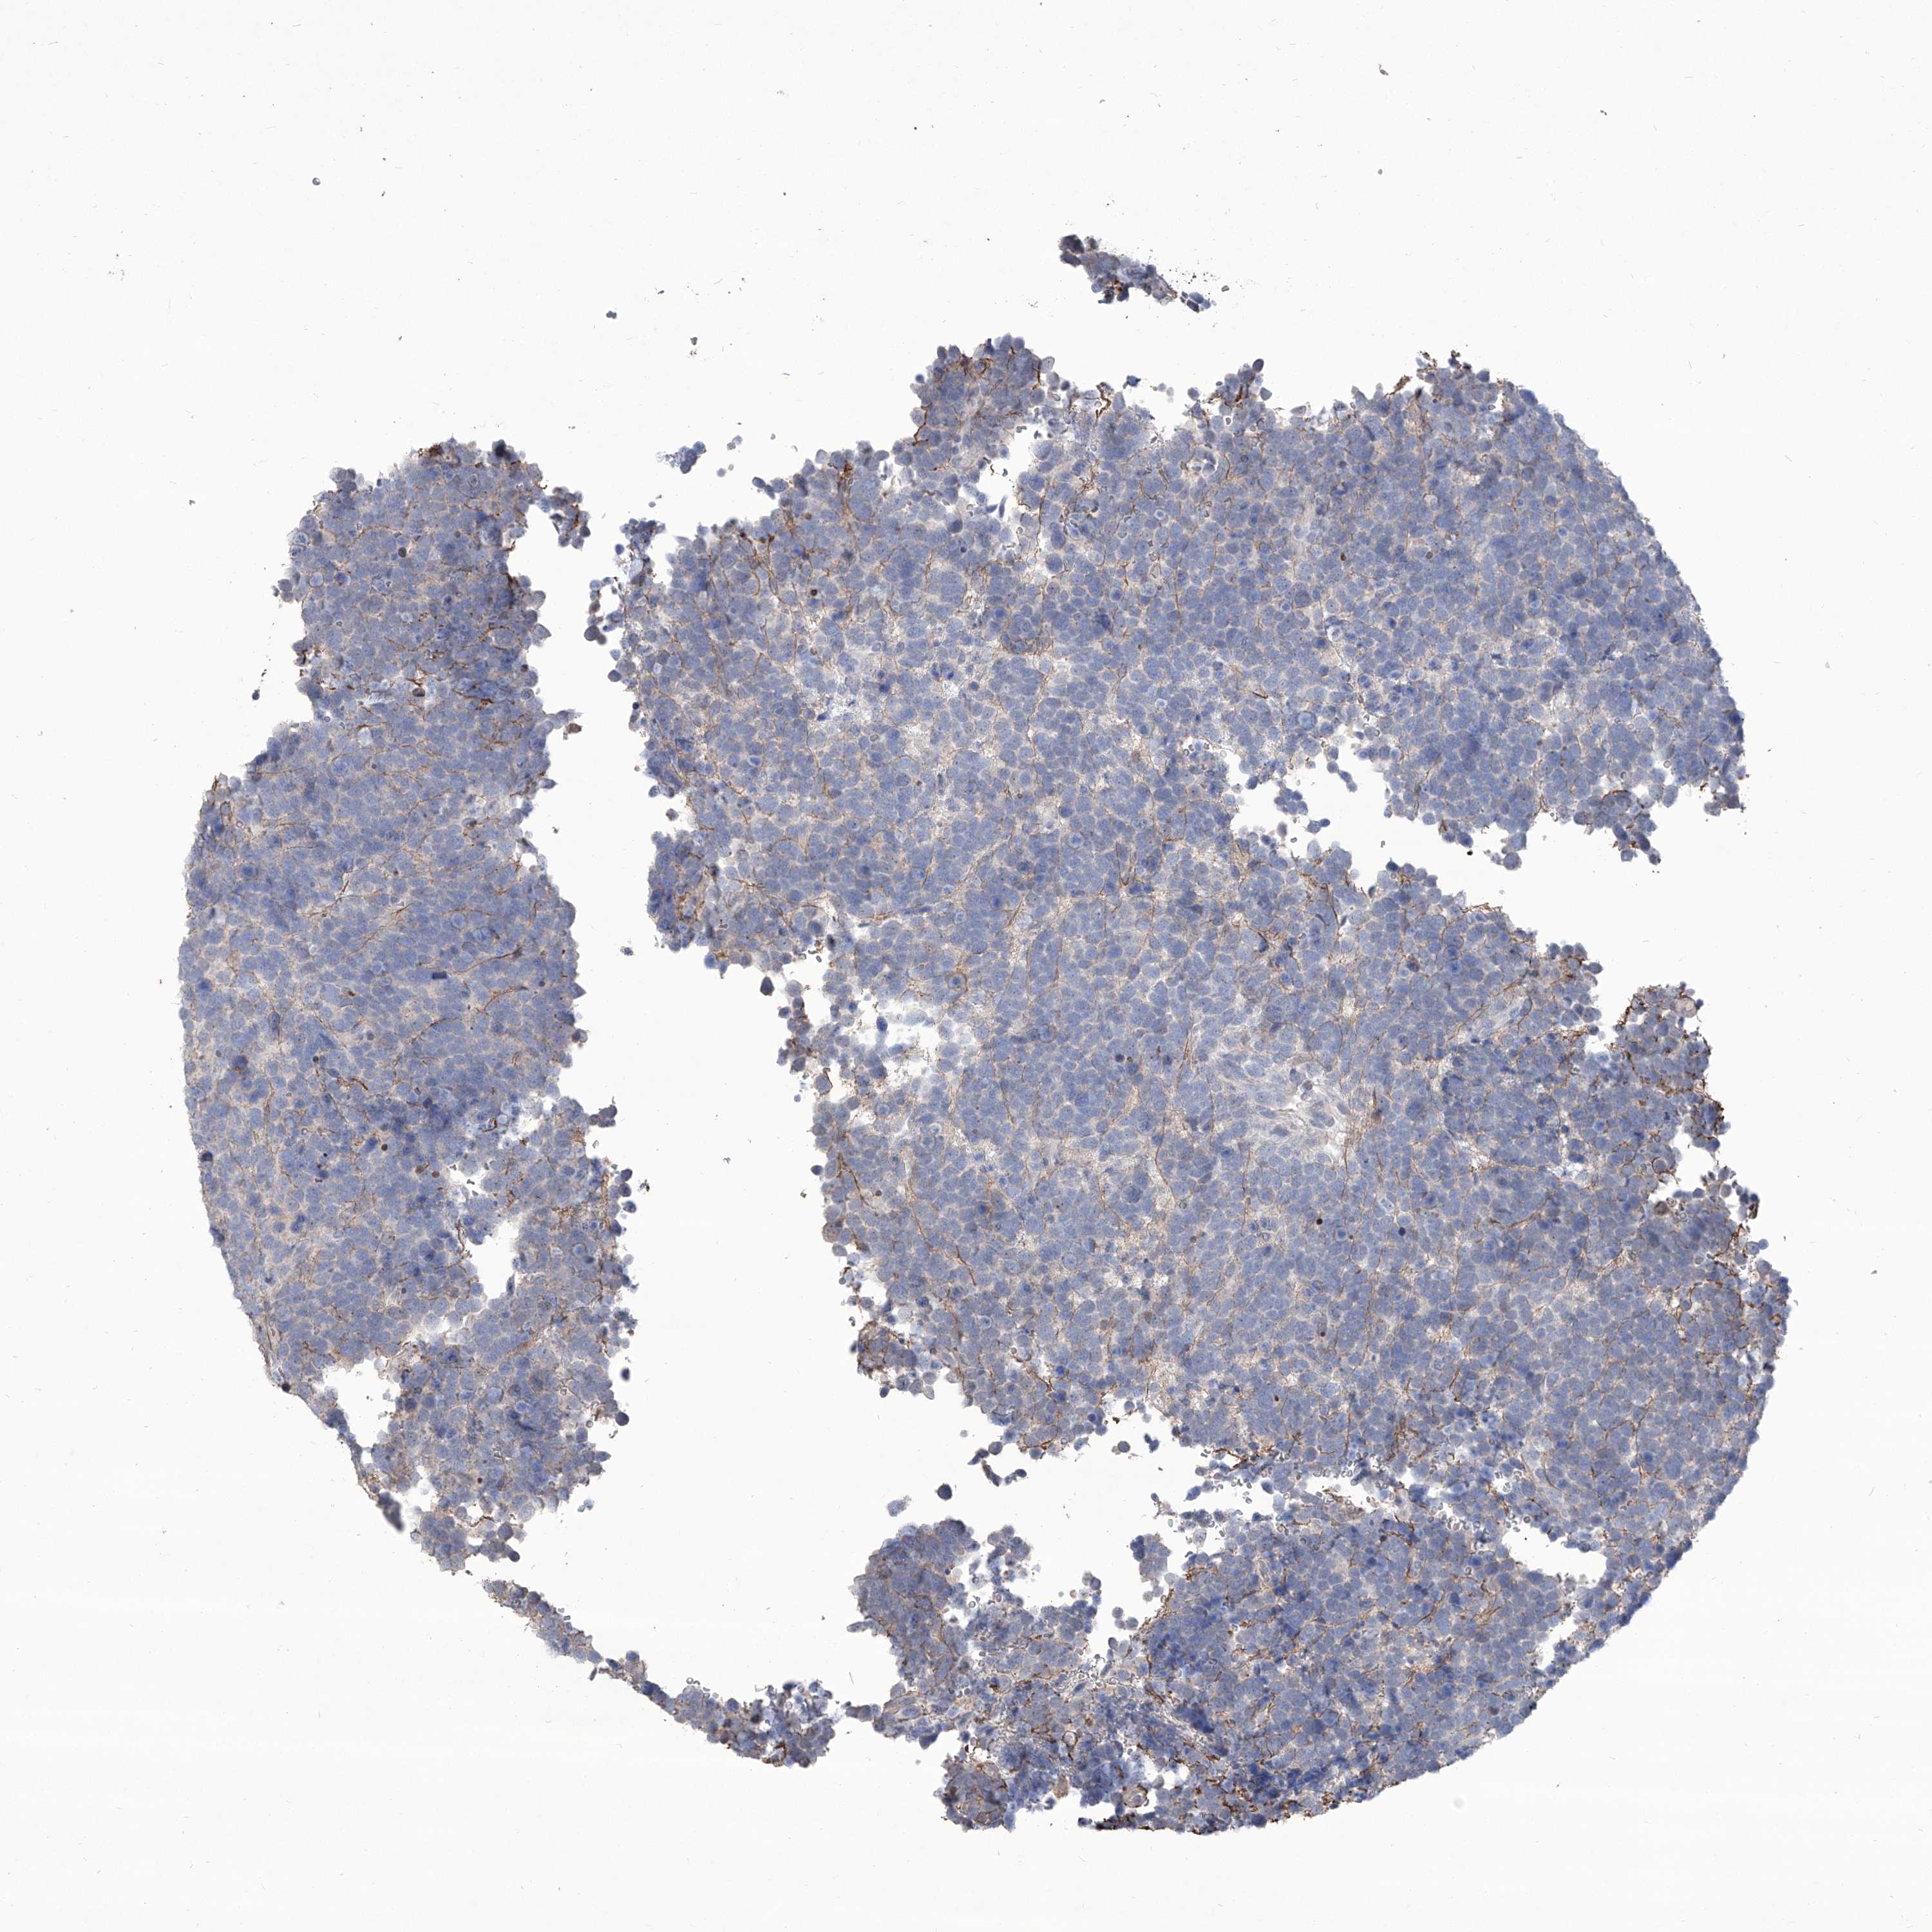

UROTHELIAL CANCER - Protein expressioni

A mouse-over function shows sample information and annotation data. Click on an image to view it in a full screen mode. Samples can be filtered based on level of antibody staining by selecting one or several of the following categories: high, medium, low and not detected. The assay and annotation is described here.

Note that samples used for immunohistochemistry by the Human Protein Atlas do not correspond to samples in the TCGA dataset.

Antibody stainingi

Antibody staining in the annotated cell types in the current human tissue is reported as not detected, low, medium, or high, based on conventional immunohistochemistry profiling in selected tissues. This score is based on the combination of the staining intensity and fraction of stained cells.

Each image is clickable and will lead to virtual microscopy that enables deeper exploration of all samples and also displays staining intensity scores, fraction scores and subcellular localization as well as patient and tissue information for each sample.

Antibody HPA031085

Antibody HPA053694

Staining

High

Medium

Low

Not detected

Intensity

Strong

Moderate

Weak

Negative

Quantity

>75%

75%-25%

<25%

None

Location

Nuclear

Cytoplasmic/membranous

Cytoplasmic/membranous,nuclear

Urothelial carcinoma, Low grade

Urothelial carcinoma, High grade

Urothelial carcinoma, NOS